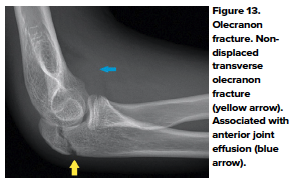

- Olecranon Fracture

- Olecranon fractures occur in children from a direct blow to the elbow or from a FOOSH. Clinical presentation includes pain and swelling with point tenderness over the olecranon. Most fractures are greenstick fractures, however, special attention should be made in regards to whether the fracture is extra-articular vs intra-articular. Always look for an associated injury, especially dislocation/fracture of the radial head.14 (Figure 13)